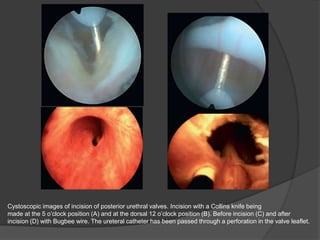

Cystoscopic images of incision of posterior urethral valves. Incision with a Collins knife being

made at the 5 o’clock position (A) and at the dorsal 12 o’clock position (B). Before incision (C) and after

incision (D) with Bugbee wire. The ureteral catheter has been passed through a perforation in the valve leaflet.

There are severalapproaches to valve ablation. Historically, it had even been successfully performed with a crochet hook passed retrograde into the urethra and feeling the hook catch the obstructing tissue. Innes Williams first described the engagement of valves with a hook, and Whitaker and Sherwood modified the hook by insulating the wire except for the very distal portion of the hook, which measures 6 to 7 Fr and could be passed at the bedside without general anesthesia while applying a small amount of diathermy when ablating the valves . With the miniaturization of endoscopes in the age of fiberoptic and, now, digital technology, cystoscopy can be accomplished in even the smallest neonate, and endoscopic valve ablation is the preferred approach at most centers today. Availability of a 7.5-Fr or 9-Fr infant cystoscope with an offset lens facilitates passage of a variety of ablating devices, including a Bugbee electrode that can be used to incise the valves at the ventral 5 o’clock and 7 o’clock positions with or without an incision on the dorsal 12 o’clock position. Alternatively, a 12 o’clock alone might suffice (Video 33.1). A wire bent at the tip and passed through a 3-Fr ureteric catheter is another option, as is the visually guided fogarty embolectomy catheter (Soliman, 2009). In an infant with a normal caliber urethra, the 9.5-Fr resectoscope may be used with a Collins

Cystoscopic images ofincision of posterior urethral valves. Incision with a Collins knife being made at the 5 o’clock position (A) and at the dorsal 12 o’clock position (B). Before incision (C) and after incision (D) with Bugbee wire. The ureteral catheter has been passed through a perforation in the valve leaflet.